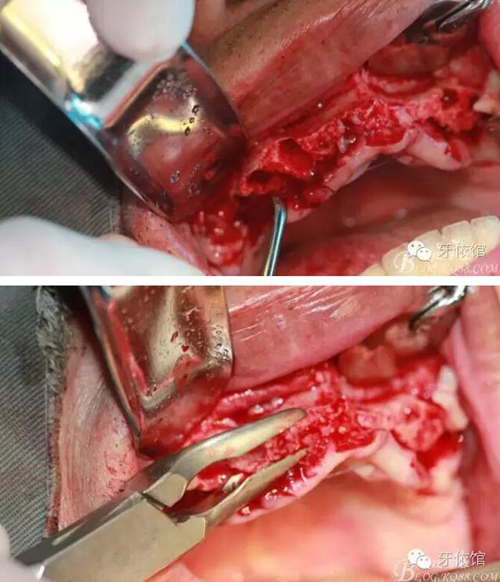

術(shù)中口內(nèi)照

降低骨高度,左右1,2骨寬度嚴(yán)重不足,決定將前牙2——2區(qū)間植體植在切牙孔內(nèi)

這個角度看1,2牙位骨寬度是不是很???僅2mm

用擴(kuò)孔鉆去除切牙孔內(nèi)神經(jīng)纖維和血管